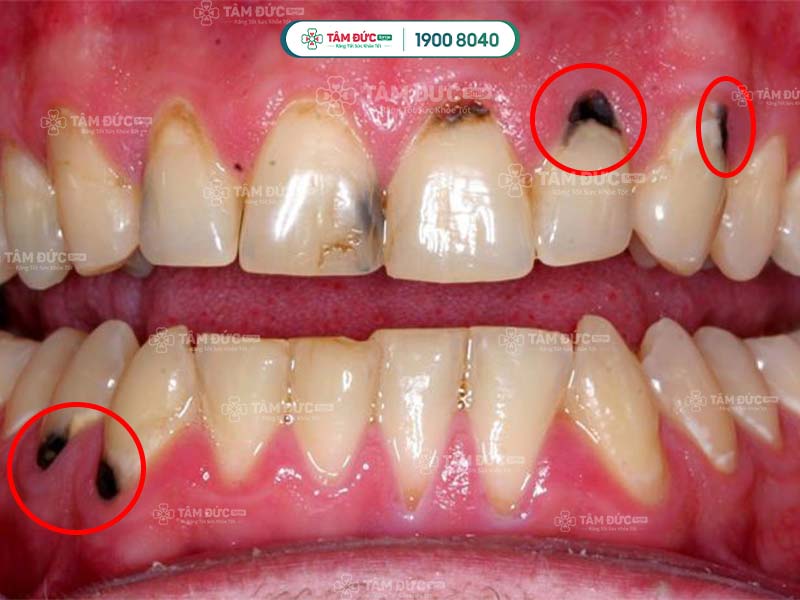

Cao răng bị đen cơ bản là cao răng thông thường, nhưng bị biến đổi màu sắc từ vàng nhạt sang đen do nhiều nguyên nhân. Điều này làm ảnh hưởng sức khỏe răng miệng và thẩm mỹ nụ cười. Cao răng đen hình thành ở thân răng hoặc chân răng, vùng tiếp xúc giữa răng và nướu.

Quý khách không thể loại bỏ cao răng đen bằng cách chải răng thông thường, mà cần đến nha khoa để được hỗ trợ. Không xử lý cao răng kịp thời sẽ làm tổn thương nướu, gây chảy máu chân răng và nhiều vấn đề khác.

Cao răng bị đen

2.4. Do sâu răng

Cao răng làm cho bề mặt răng xuất hiện những lỗ nhỏ li ti. Nếu Quý khách không điều trị sâu răng kịp thời, các lỗ li ti lan rộng và làm cho cao răng biến thành màu đen.

Cao răng bị đen là dấu hiệu cảnh báo sâu răng đang tiến triển